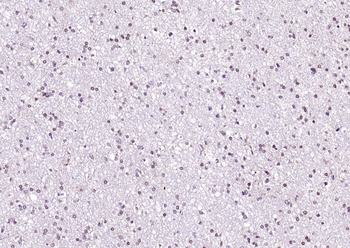

RARB Rabbit Polyclonal Antibody [orb11327]

FC, ICC, IF, IHC-Fr, IHC-P, WB

Bovine, Canine, Gallus, Porcine, Rat

Human, Mouse

Rabbit

Polyclonal

Unconjugated

50 μl, 100 μl, 200 μlTIG2 Rabbit Polyclonal Antibody [orb11481]